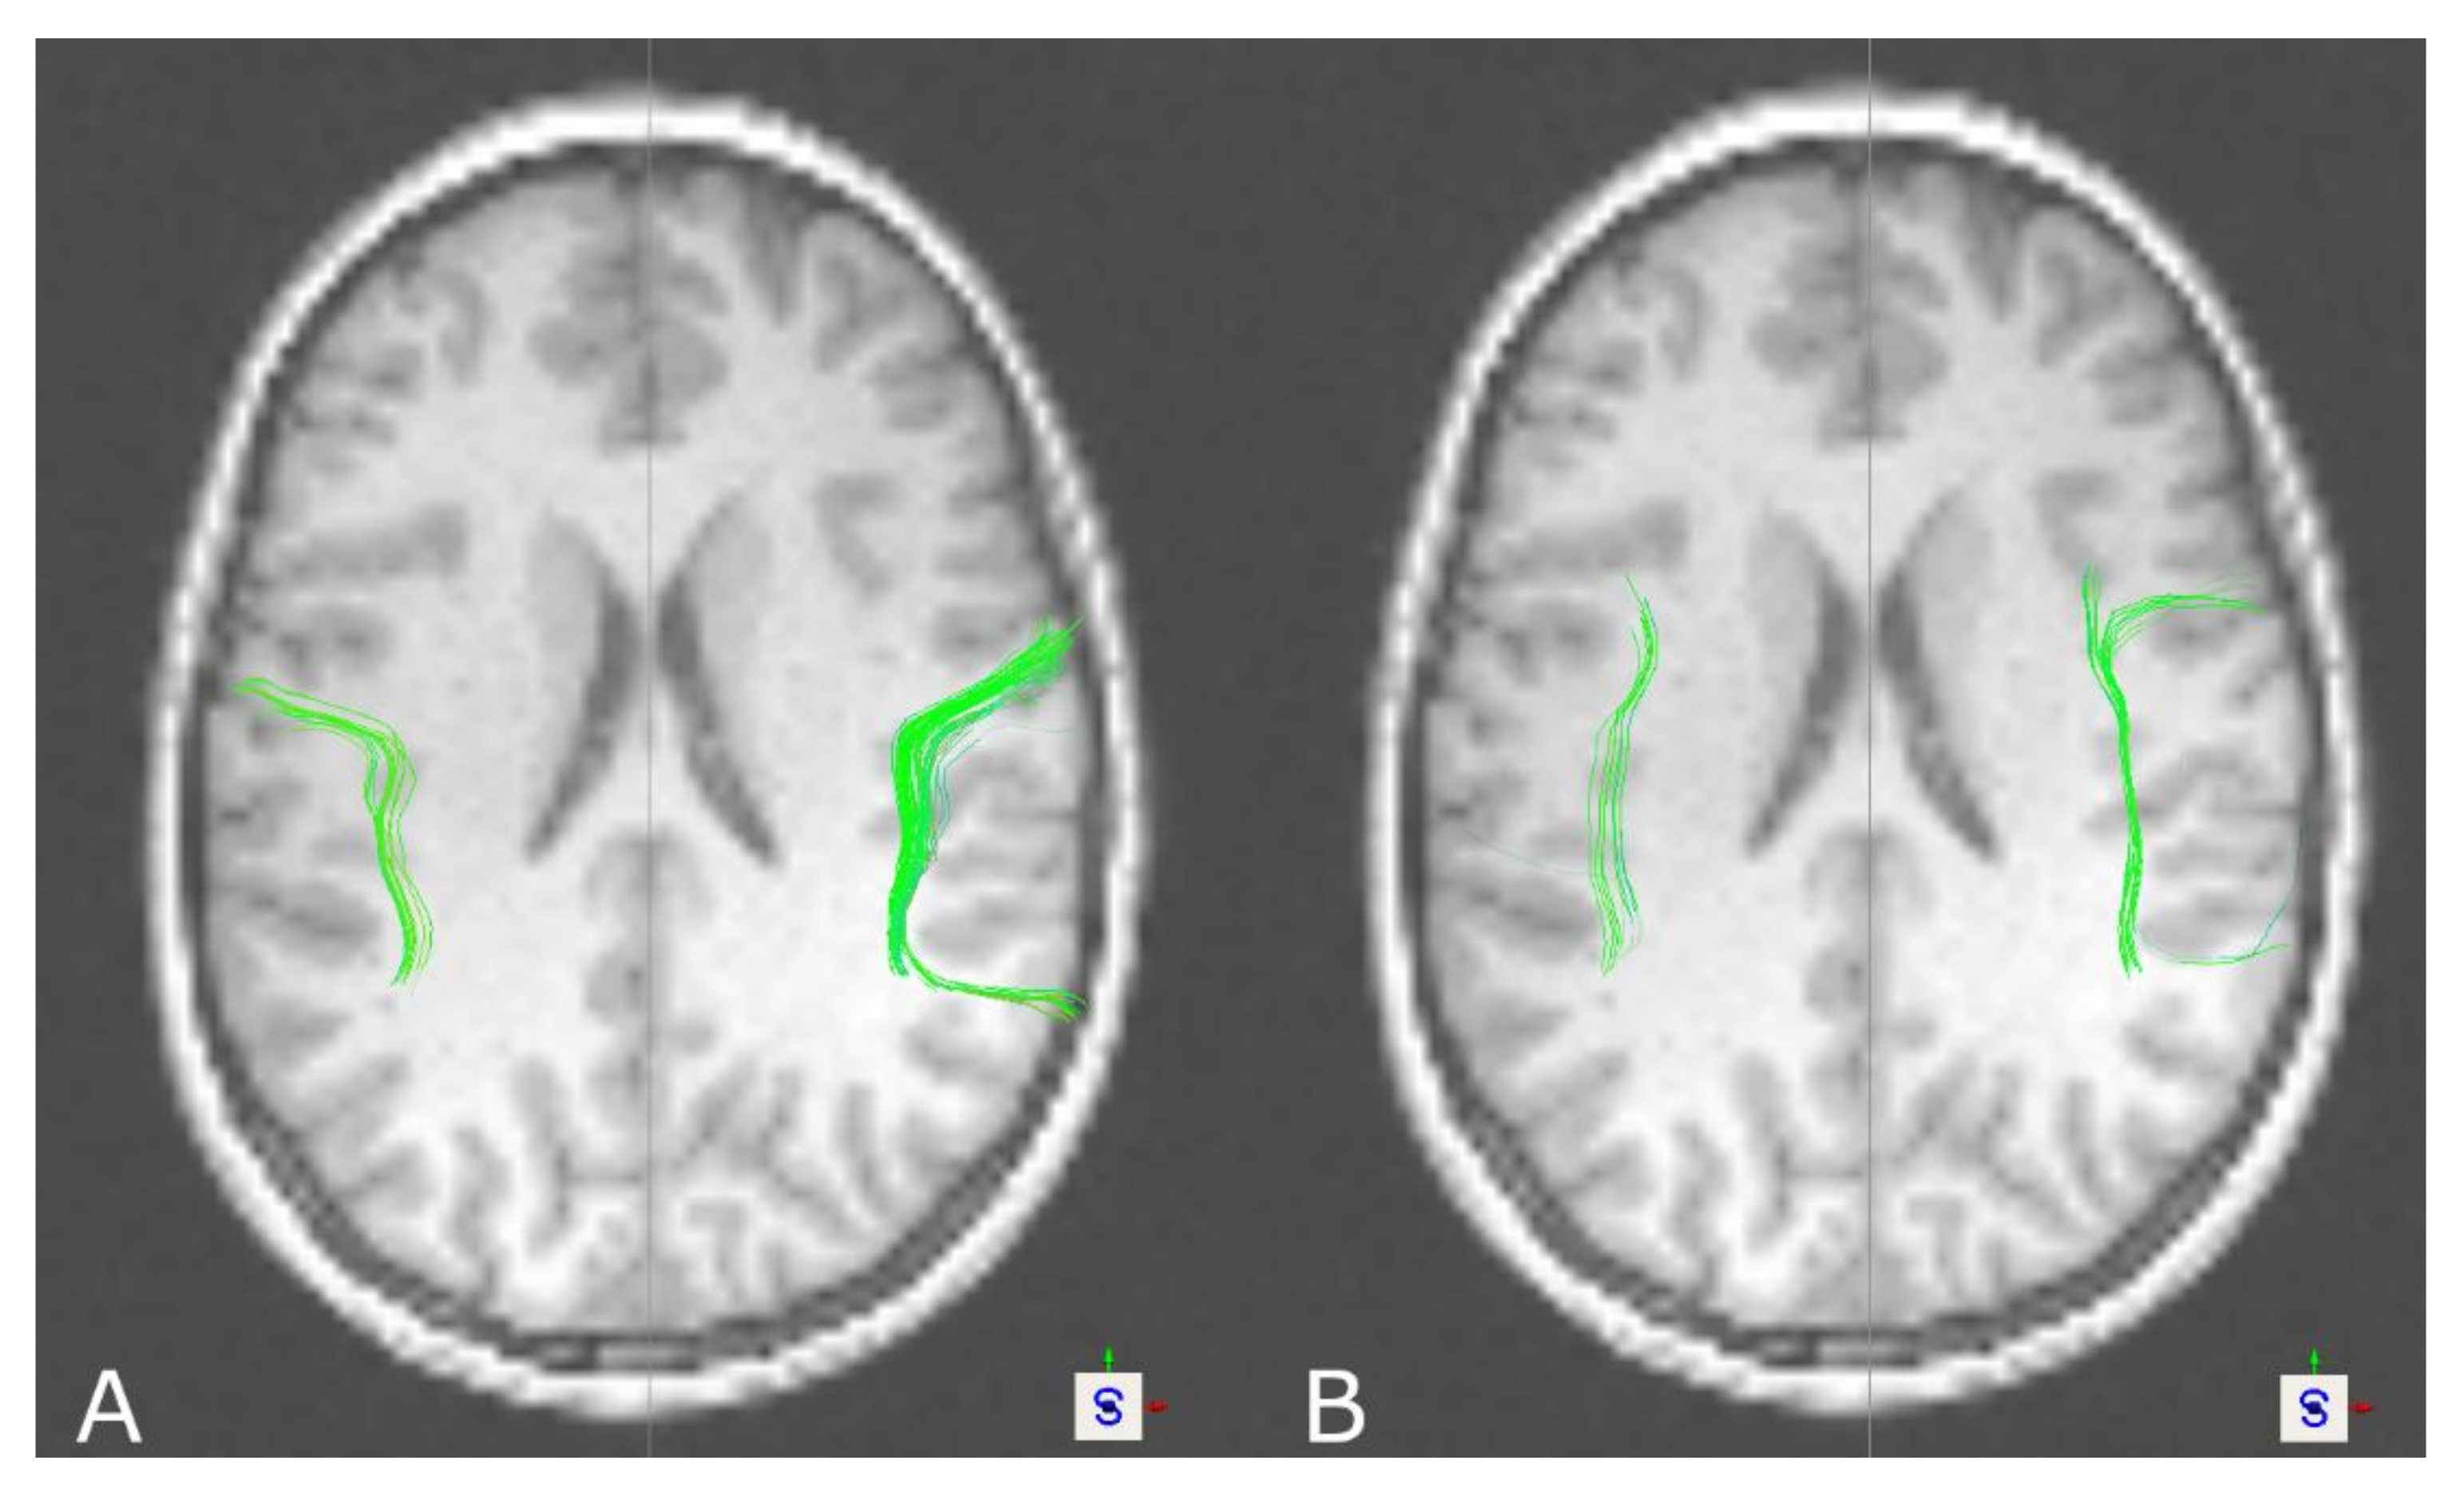

3.1. The Corticospinal Tract

3.3. The Arcuate Fascicle